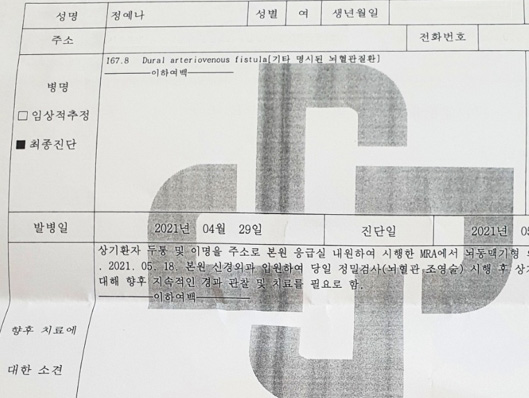

Diagnosis before healing

Ō¢▓ Suspected cerebral artery malformation was observed in the MRA performed after visiting the emergency room of the hospital for the above patientŌĆÖs headache and tinnitus. On May 18, 2021, he was admitted to the neurosurgery of the hospital and was diagnosed with the above diagnosis after performing a detailed examination (Cerebrovascular angiography) on the same day. This requires continuous follow-up and treatment in the future.

After that, I had a hard time working due to headaches and I couldnŌĆÖt sleep at night. The test result was ŌĆścerebral venous aneurysmŌĆÖ, and I heard that I had to undergo surgery. (Photo: Diagnosis before being healing)